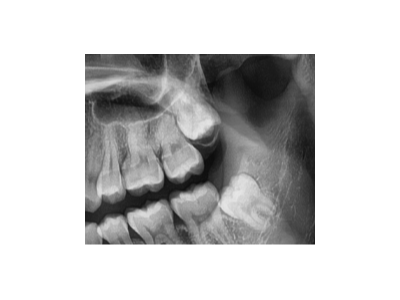

既然「智齒」不宜久留,為什么不能一次性拔掉?

智齒又被稱為第三磨牙,一般有1~4顆不等。由于生長空間有限,很多智齒無法正常萌出,它會歪著長、橫著長,甚至野蠻生長……